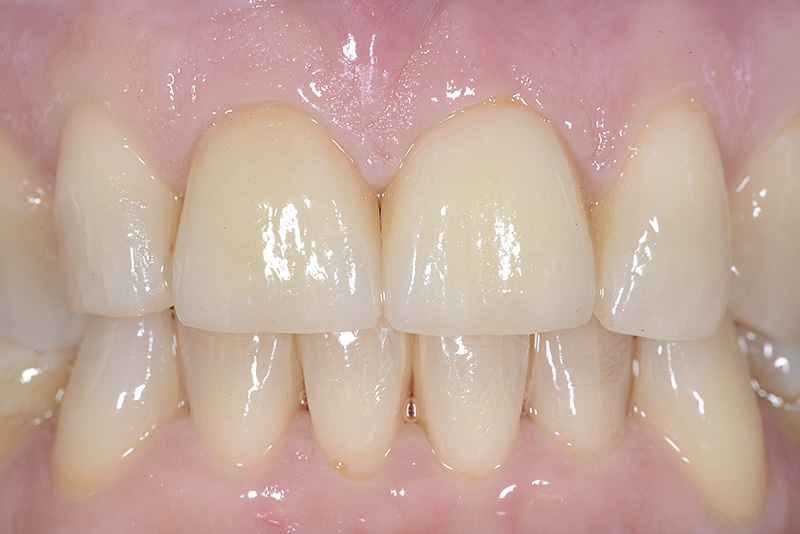

PREMESSA: in seguito all’estrazione dell’incisivo laterale superiore di destra, resasi necessaria per cause batteriche, si decide di affrontare il caso con il posizionamento di un impianto in sostituzione dell’elemento mancante dopo guarigione del sito infetto. Con tecniche rigenerative sia dei tessuti ossei mancanti a causa dell’infezione pregressa, sia dei tessuti gengivali che appaiono inizialmente troppo spostati in alto, si ripristina una corretta morfologia delle parabole (contorni) gengivali e delle papille interdentali (triangoli di gengiva tra due denti vicini).

Vengono utilizzati 2 tipi di provvisori: il primo, cementato ai denti vicini, viene utilizzato dal momento dell’estrazione del dente fino ad impianto osteointegrato (circa 6 mesi); il secondo, avvitato direttamente all’impianto, ha una funzione di prova estetica ma soprattutto di guida per la maturazione dei tessuti gengivali peri-implantari portandoli verso la maturazione completa prima di posizionare la corona finale in disilicato di litio.